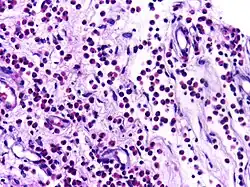

![]() | Dysgerminoma | Dysgerminoma characterized by uniform cells resembling primordial germ cells separated by fibrous septa with lymphocytes. | Category: Histopathology of ovarian dysgerminoma | Ovarian dysgerminoma |